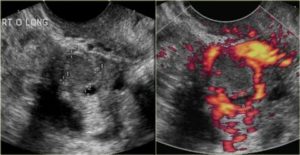

На УЗИ желтое тело определяется как округлое неоднородное образование.

Его видно и при методике исследования через брюшную стенку (трансабдоминальная методика УЗИ), но более достоверные результаты диагностики получают при трансвагинальном методе с использованием внутривагинального датчика.

Как выглядит желтое тело на УЗИ?

- Неправильной формы, с толстым краем и даже валиком.

- С неровным «фестончатым» краем.

- Находится в яичнике на месте бывшего фолликула. Иногда частично представляет собой сгусток крови, образовавшийся после разрыва фолликула.

- Внутренняя его структура на УЗИ крайне разнообразна, может включать кистозные полости и даже кровоизлияния.

- Кровоток при ЦДК по периферии очень активный. Это неудивительно, ведь временный орган должен хорошо кровоснабжаться для нормальной его работы.

Выглядит на УЗИ желтое тело, как анэхогенное образование. Отсутствие эхогенности обусловлено его содержимым. Внутри находится жидкость, обрамленная ровным контуром без дополнительных камер. Находится желтое тело на поверхности яичника, где ранее располагался доминантный фолликул. Дополнительным показателем функции желтого тела становится толщина эндометрия.

Описание лютеиновой железы на УЗИ:

| Параметры | Эхопризнаки | Как выглядит |

| Внешний вид | Гетерогенное анэхогенное образование | На яичнике округлое темно-серое пятно с черными вкраплениями и единичными белыми точками |

| Структура | Гиперэхогенное образование с крупными зонами низкой плотности (гипо- или анэхогенными очагами) | Серое пятно с большой площадью затемнений. Окрашены черным места скопления крови, локализации сосудов |

| Размер | В норме до 30 мм, при образовании кисты – более 3 см | Диаметр ЖТ сверяют с нормой по фазам желтого тела |